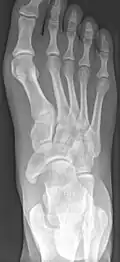

Radiographie du pied montrant un os naviculaire accessoire

Les radiographies sont généralement commandées pour confirmer le diagnostic. S'il y a une douleur ou une inflammation en cours, une IRM ou d'autres tests d'imagerie avancés peuvent être utilisés pour évaluer davantage la condition.

Images radiologiques